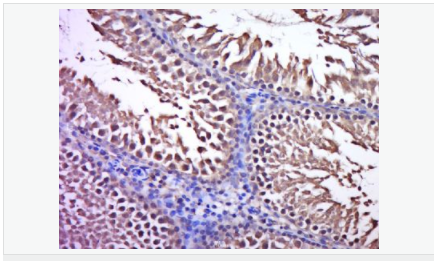

| 產(chǎn)品應(yīng)用 | WB=1:500-2000 ELISA=1:5000-10000 IHC-P=1:100-500 IHC-F=1:100-500 ICC=1:100-500 IF=1:100-500 (石蠟切片需做抗原修復(fù)) not yet tested in other applications. optimal dilutions/concentrations should be determined by the end user. |

| 產(chǎn)品介紹 | C3orf32 (chromosome 3 open reading frame 32), also known as fls485, is a 353 amino acid protein encoded by a gene that maps to human chromosome 3p26.1. Chromosome 3 is made up of approximately 214 million bases encoding over 1,100 genes. Notably, there is a chemokine receptor gene cluster and a variety of human cancer related loci on chromosome 3. Particular regions of the chromosome 3 short arm are deleted in many types of cancer cells. Key tumor suppressing genes on chromosome 3 encode apoptosis mediator RASSF1, cell migration regulator HYAL1 and angiogenesis suppressor SEMA3B. Marfan Syndrome, porphyria, von Hippel-Lindau syndrome, osteogenesis imperfecta and Charcot-Marie-Tooth disease are a few of the numerous genetic diseases associated with chromosome 3. Subcellular Location: Cytoplasm. Tissue Specificity: Expressed in enterocytes of small and large intestinal mucosa (at protein level). Expressed in enterocytes, chromaffine and interstitial cells. SWISS: Q9Y2M2 Gene ID: 51066 Database links: Entrez Gene: 51066 Human SwissProt: Q9Y2M2 Human Unigene: 561182 Human Unigene: 740735 Human Important Note: This product as supplied is intended for research use only, not for use in human, therapeutic or diagnostic applications. |